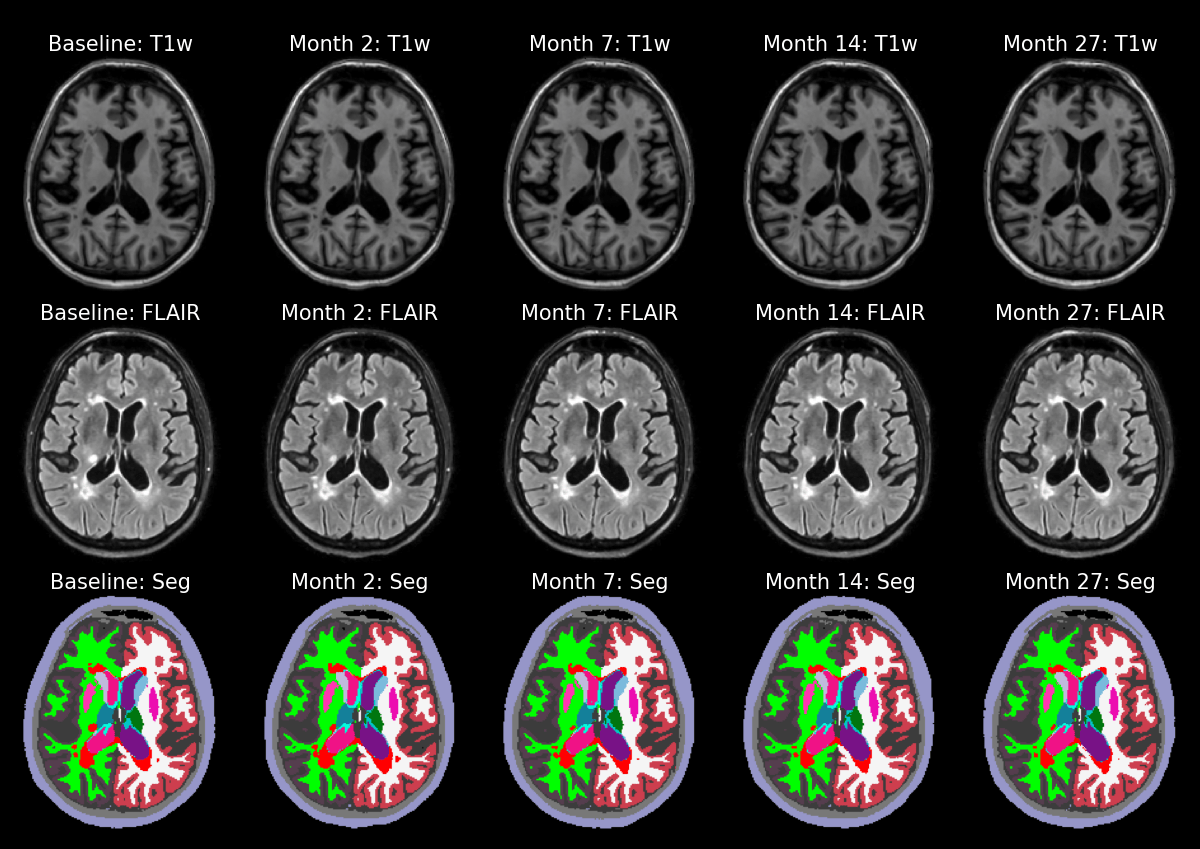

In a previous post, I described how to obtain brain segmentations using a Gaussian Mixture Model (GMM). One of the limitations of this brain segmentation